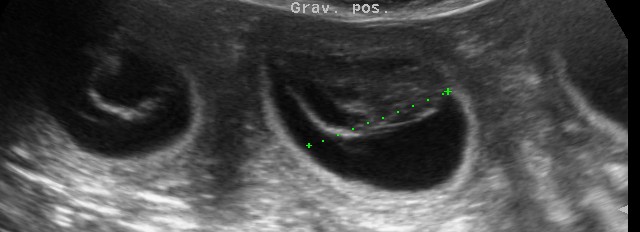

ist trächtig !!

nun sind wir gespannt ob Mendel Recht hat, demnach erwarten wir 25% weiße; 50%maskenfalbe; 25% schwarze Welpen!